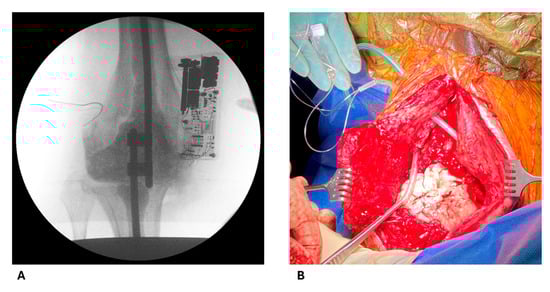

4.2. Intraoperative Procedures